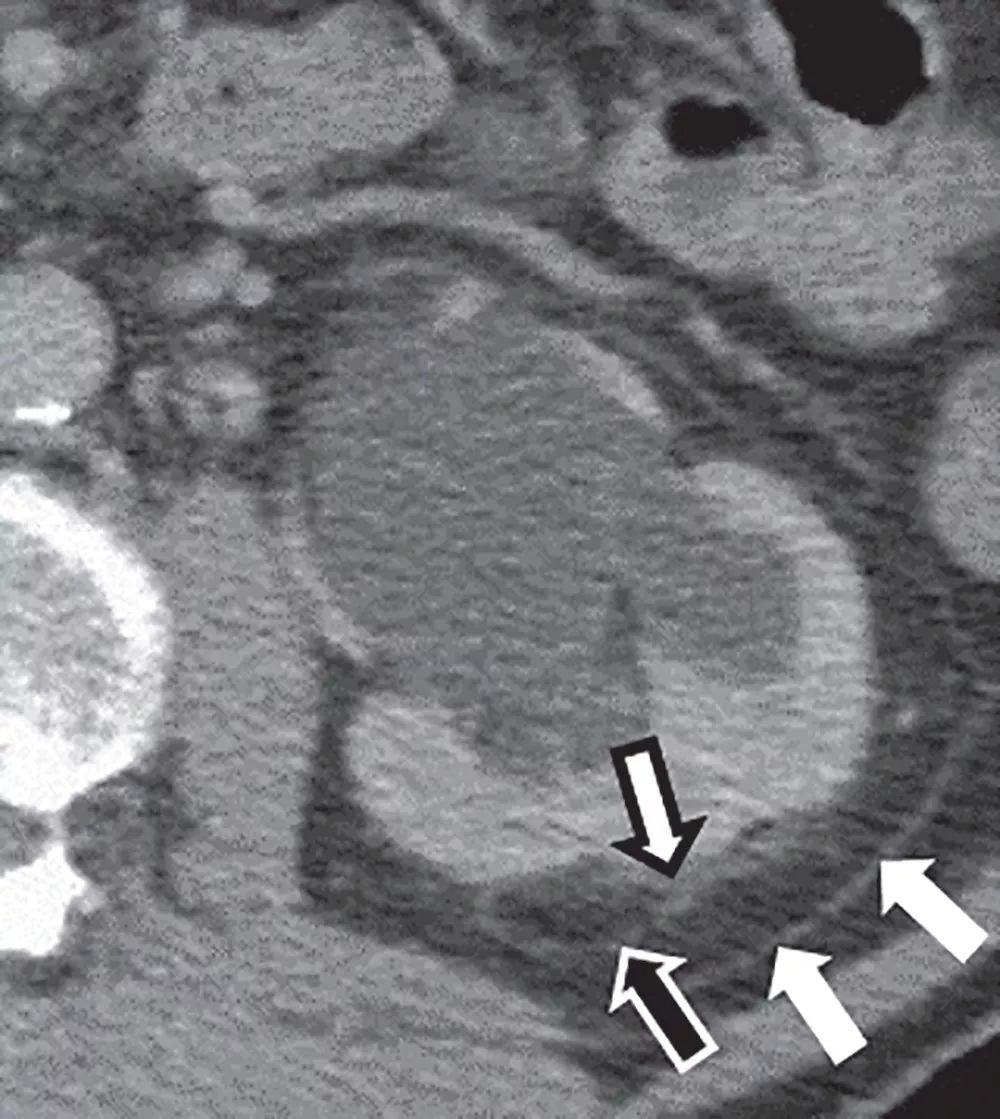

输入袢梗阻